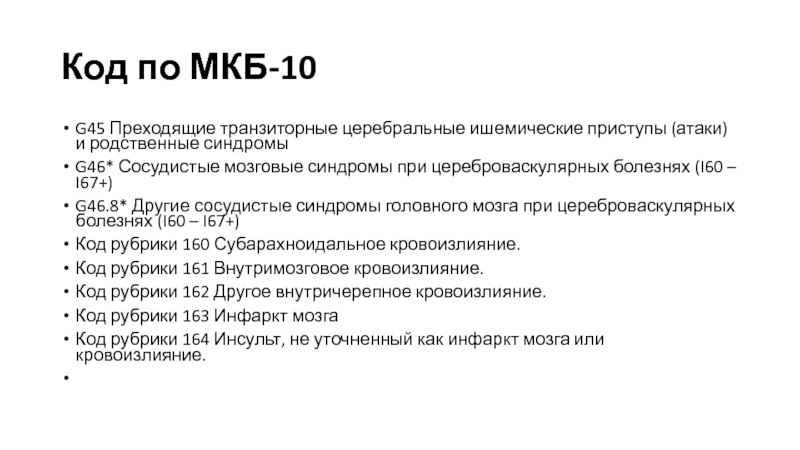

Код мкб 10 атерома головы

Код мкб 10 атерома головы 109 фото